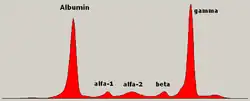

In MM, the abnormal plasma cells produce abnormal antibodies, which can cause kidney problems and overly thick blood.[10] The plasma cells can also form a mass in the bone marrow or soft tissue.[10] When one tumor is present, it is called a plasmacytoma; more than one is called multiple myeloma.[10] Multiple myeloma is diagnosed based on blood or urine tests finding abnormal antibody proteins (often using electrophoretic techniques revealing the presence of a monoclonal spike in the results, termed an m-spike), bone marrow biopsy finding cancerous plasma cells, and medical imaging finding bone lesions.[6] Another common finding is high blood calcium levels.[6]

The globulin level may be normal in established disease. A doctor may request protein electrophoresis of the blood and urine, which might show the presence of a paraprotein (monoclonal protein, or M protein) band, with or without reduction of the other (normal) immunoglobulins (known as immune paresis). One type of paraprotein is the Bence Jones protein, which is a urinary paraprotein composed of free light chains. Quantitative measurements of the paraprotein are necessary to establish a diagnosis and to monitor the disease. The paraprotein is a specific immunoglobulin (or fragment of immunoglobulin) originally produced by the mutated plasma cell, which began to multiply and is now produced by the entire line of malignant cells.[66]

In theory, multiple myeloma can produce all classes of immunoglobulin, but IgG paraproteins are most common, followed by IgA and IgM. IgD and IgE myeloma are very rare. In addition, light and or heavy chains (the building blocks of antibodies) may be secreted in isolation: κ- or λ-light chains or any of the five types of heavy chains (α-, γ-, δ-, ε- or μ-heavy chains). People without evidence of a monoclonal protein may have "nonsecretory" myeloma (not producing immunoglobulins); this represents about 3% of all people with multiple myeloma.[67]

Additional findings may include a raised calcium level (when osteoclasts are breaking down bone, releasing it into the bloodstream), raised serum creatinine level due to reduced kidney function, which is mainly due to casts of paraprotein deposition in the kidney, although the cast may also contain complete immunoglobulins, Tamm-Horsfall protein and albumin.[68]

Other useful laboratory tests include quantitative measurements of IgA, IgG, and IgM to look for immune paresis, and beta-2 microglobulin, which provides prognostic information. On peripheral blood smear, the rouleaux formation of red blood cells is commonly seen, though this is not specific.

The recent introduction of a commercial immunoassay for the measurement of free light chains potentially offers an improvement in monitoring disease progression and response to treatment, particularly where the paraprotein is difficult to measure accurately by electrophoresis (for example, in light chain myeloma, or where the paraprotein level is very low). Initial research also suggests that measuring free light chains may also be used, in conjunction with other markers, for assessment of the risk of progression from MGUS to multiple myeloma.[69]

This assay, the serum free light chain assay, has recently been recommended by the International Myeloma Working Group for the screening, diagnosis, prognosis, and monitoring of plasma cell dyscrasias.[70]